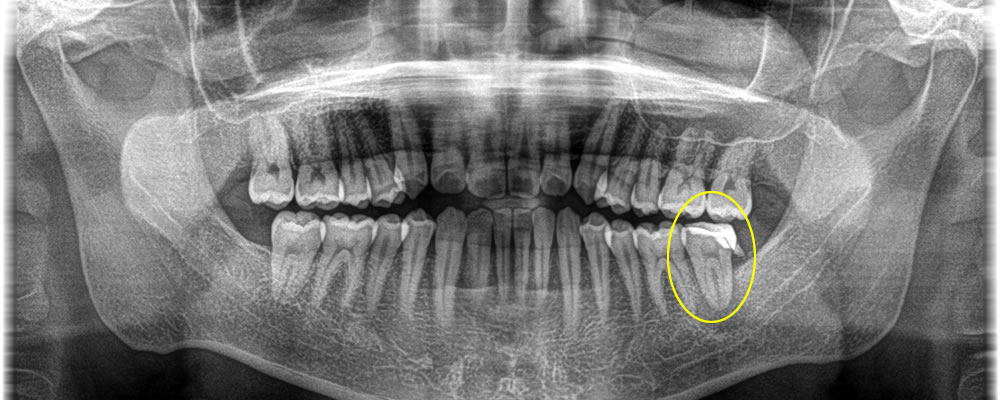

レントゲンでの検査の結果、他院で治療した補綴物の中に二次むし歯ができ神経まで到達し、根っこの先まで膿が溜まってしまったことが痛みの原因であったことがわかりました。